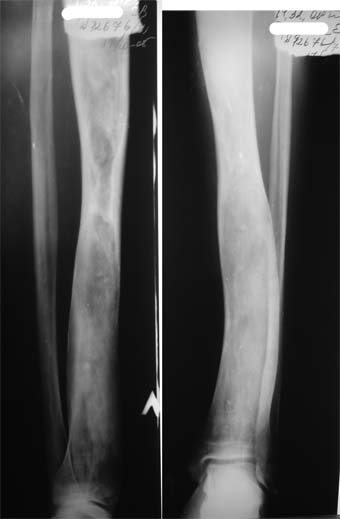

Коллеги!Пациент Д., 35 лет, В 1985 году был поставлен диагноз гемигипоплазия правой нижней конечности. Укорочение 5 см, в 1987 году остеотомия правого бедра, аппарат 4 месяца, удлинили на 2 см из-за нагноения спиц аппарат сняли. В настоящее время Жалобы на дискомфорт, тяжесть в левом бедре, голени при длительной ходьбе, при длительном лежании на левом бедре. Эти жалобы беспокоят втечение 5-6 лет. В 1999 году выявили "изменения" (со слов больного, выписки нет на руках) бедренной кости и костей голени слева. Тогда же предложили в ЦИТО срочно делать какую-то операцию. При осмотре: Правая нижняя конечность. Имеются рубцы на правом бедре по наружной и внутренней поверхностям. Ограничения движений в коленном суставе нет. Кровоснабжение, иннервация сохранены. Левая нижняя конечность. Левое бедро увеличено в объеме, при пальпации пальпируется бедренная кость большего диаметра по сравнению с левым бедром. Пальпация безболезненна. Голень обычной формы. Объем движений в суставах полный. Кровоснабжение, иннервация сохранены. Имеется разница в длине конечностей правая короче на 4-5 см за счет бедра и голени. В приложении вид больного и рентгенограммы бедра 2001 год и 2005 год. Что бы это могло быть? О чем можно думать? Онкология? С уважением Коробушкин Глеб Владимирович Российский государственный медицинский университет кафедра травматологии, ортопедии и ВПХ, доцент

В настоящее время имеется умеренный рубцовый процесс правого бедра не мешающий на объем движений в суставах. В коленном суставе слева бедро обычное, голень - булавовидное утолщение проксимального конца большеберцовой кости. На рентгенограммах тотальное поражение кости с увлечением в процесс проксимального эпиметафиза, поражение характерно для болезни Campanatsehi

У больного полиоссальноая форма фиброзной дисплазии с поражение левой бедренной и большеберцовой кости. На рентгенограммах - тотальное разрастание и остончение кортикального слоя. Имеется удлинение левой нижней конечности на 2,5-3 см за счет голени. Больному показано оперативное лечение левой большеберцовой кости.